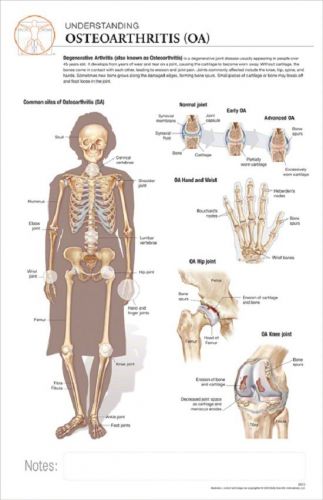

11 x 17 Post-It Disease Chart: OSTEOARTHRITIS